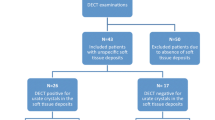

We retrospectively identified all patients with suspected gout who underwent DECT in the period from September 2011 through July 2014 and additionally had an MRI of the same anatomical region. All patients had an unclear clinical presentation and suspicion of gouty arthritis that occurred either when first presenting at our hospital or later in the course of the treatment. DECT was performed to search for gouty tophi, and MRI in clinical routine to detect inflammatory changes. The report database and hospital PACS (picture archiving and communication system) were used to find those examinations. From the 24 patients who met these criteria, we selected those who had an interval of 3 months or less between DECT and MRI. Eleven patients (six men and five women aged from 45 to 81 years (mean age, 62.2 years) with an interval of 0–82 days (mean, 40 days) between examinations met our criteria and were included. Details of the study population are summarized in Table 1.